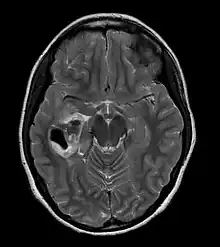

| CT scan of a brain with pleomorphic xanthoastrocytoma. The classic radiographic appearance is one of a superficially situated tumor, here a mural nodule, associated with an underlying cyst. |

- A CT scan of the brain, and/or an MRI scan of the brain and spine, will be performed. A special dye may be injected into a vein before these scans to provide contrast and make tumors easier to see.